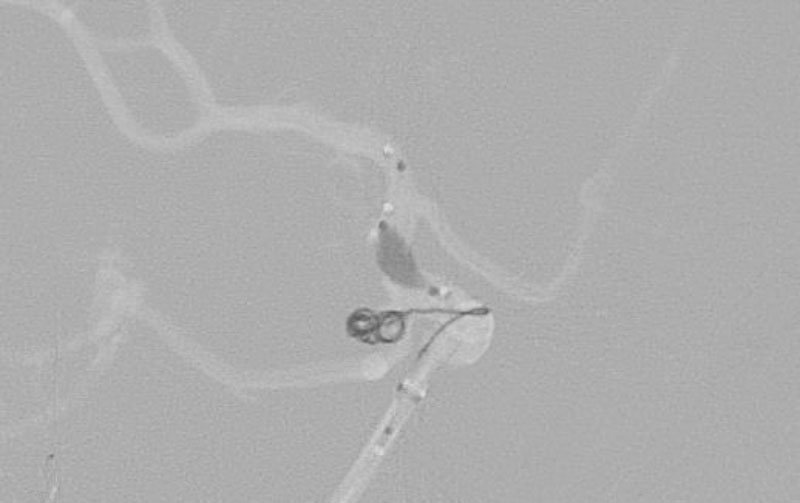

No.1628 手術中